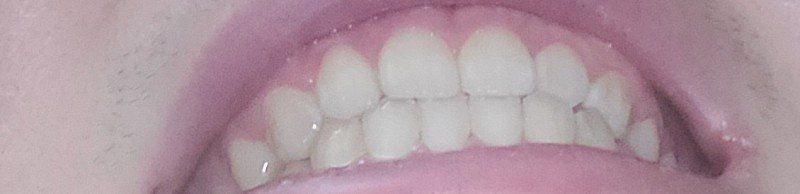

2.앞니도 윗니가 아랫니를 포개긴 하는데 사이 공간없이 딱붙긴해요 원래 살짝 띄워져야하나요?

• 4번 째 사진

2.앞니도 윗니가 앞으로 나오는 것이 정상입니다. 사진에서는 윗니가 앞으로 나온 양이 적기는 하지만 정상 범주입니다.

1. 이상적으로 완전한 교합은 없습니다. 일부 교합이 맞지 않을 수 있으며 저작시 큰 불편감이 없다면 치료 대상이 아닙니다.

2. 사람에 따라서 닿는 부위가 조금씩 다를 수 있습니다. 지금 사진으로는 정확한 판단이 어려우며 전반적인 구강검사 및 방사선 사진 등이 필요해보입니다.